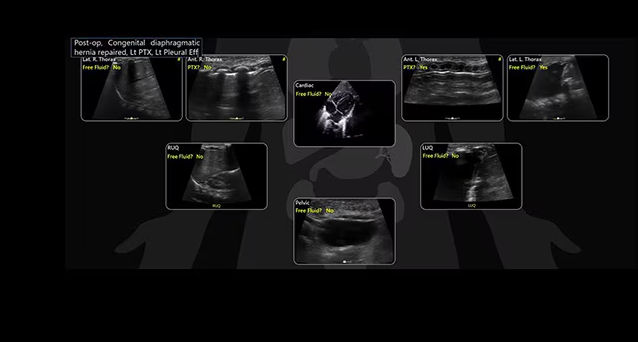

Quickly assess patient status in trauma cases with eFAST Tool

Allows users to map key areas of the body in a structural way that is intuitive and aligned with clinical workflows. Also saves keystrokes and helps provide consistent reports from user to user.

Take a structured approach to patient assessment with eFAST tool

Users can easily assess patient status with this tool that simplifies scanning order, documentation, image storage and review.

• Scan different zones sequentially, in a predetermined order, or in any order you desire.

• Document findings with single keystrokes and touch screen controls.

• Store images by using a visual anatomical diagram, with next step recommendations provided.

• Label each zone with the relevant finding while scanning.

• View a summary during or after the exam, showing the stored images superimposed over the anatomical diagram.